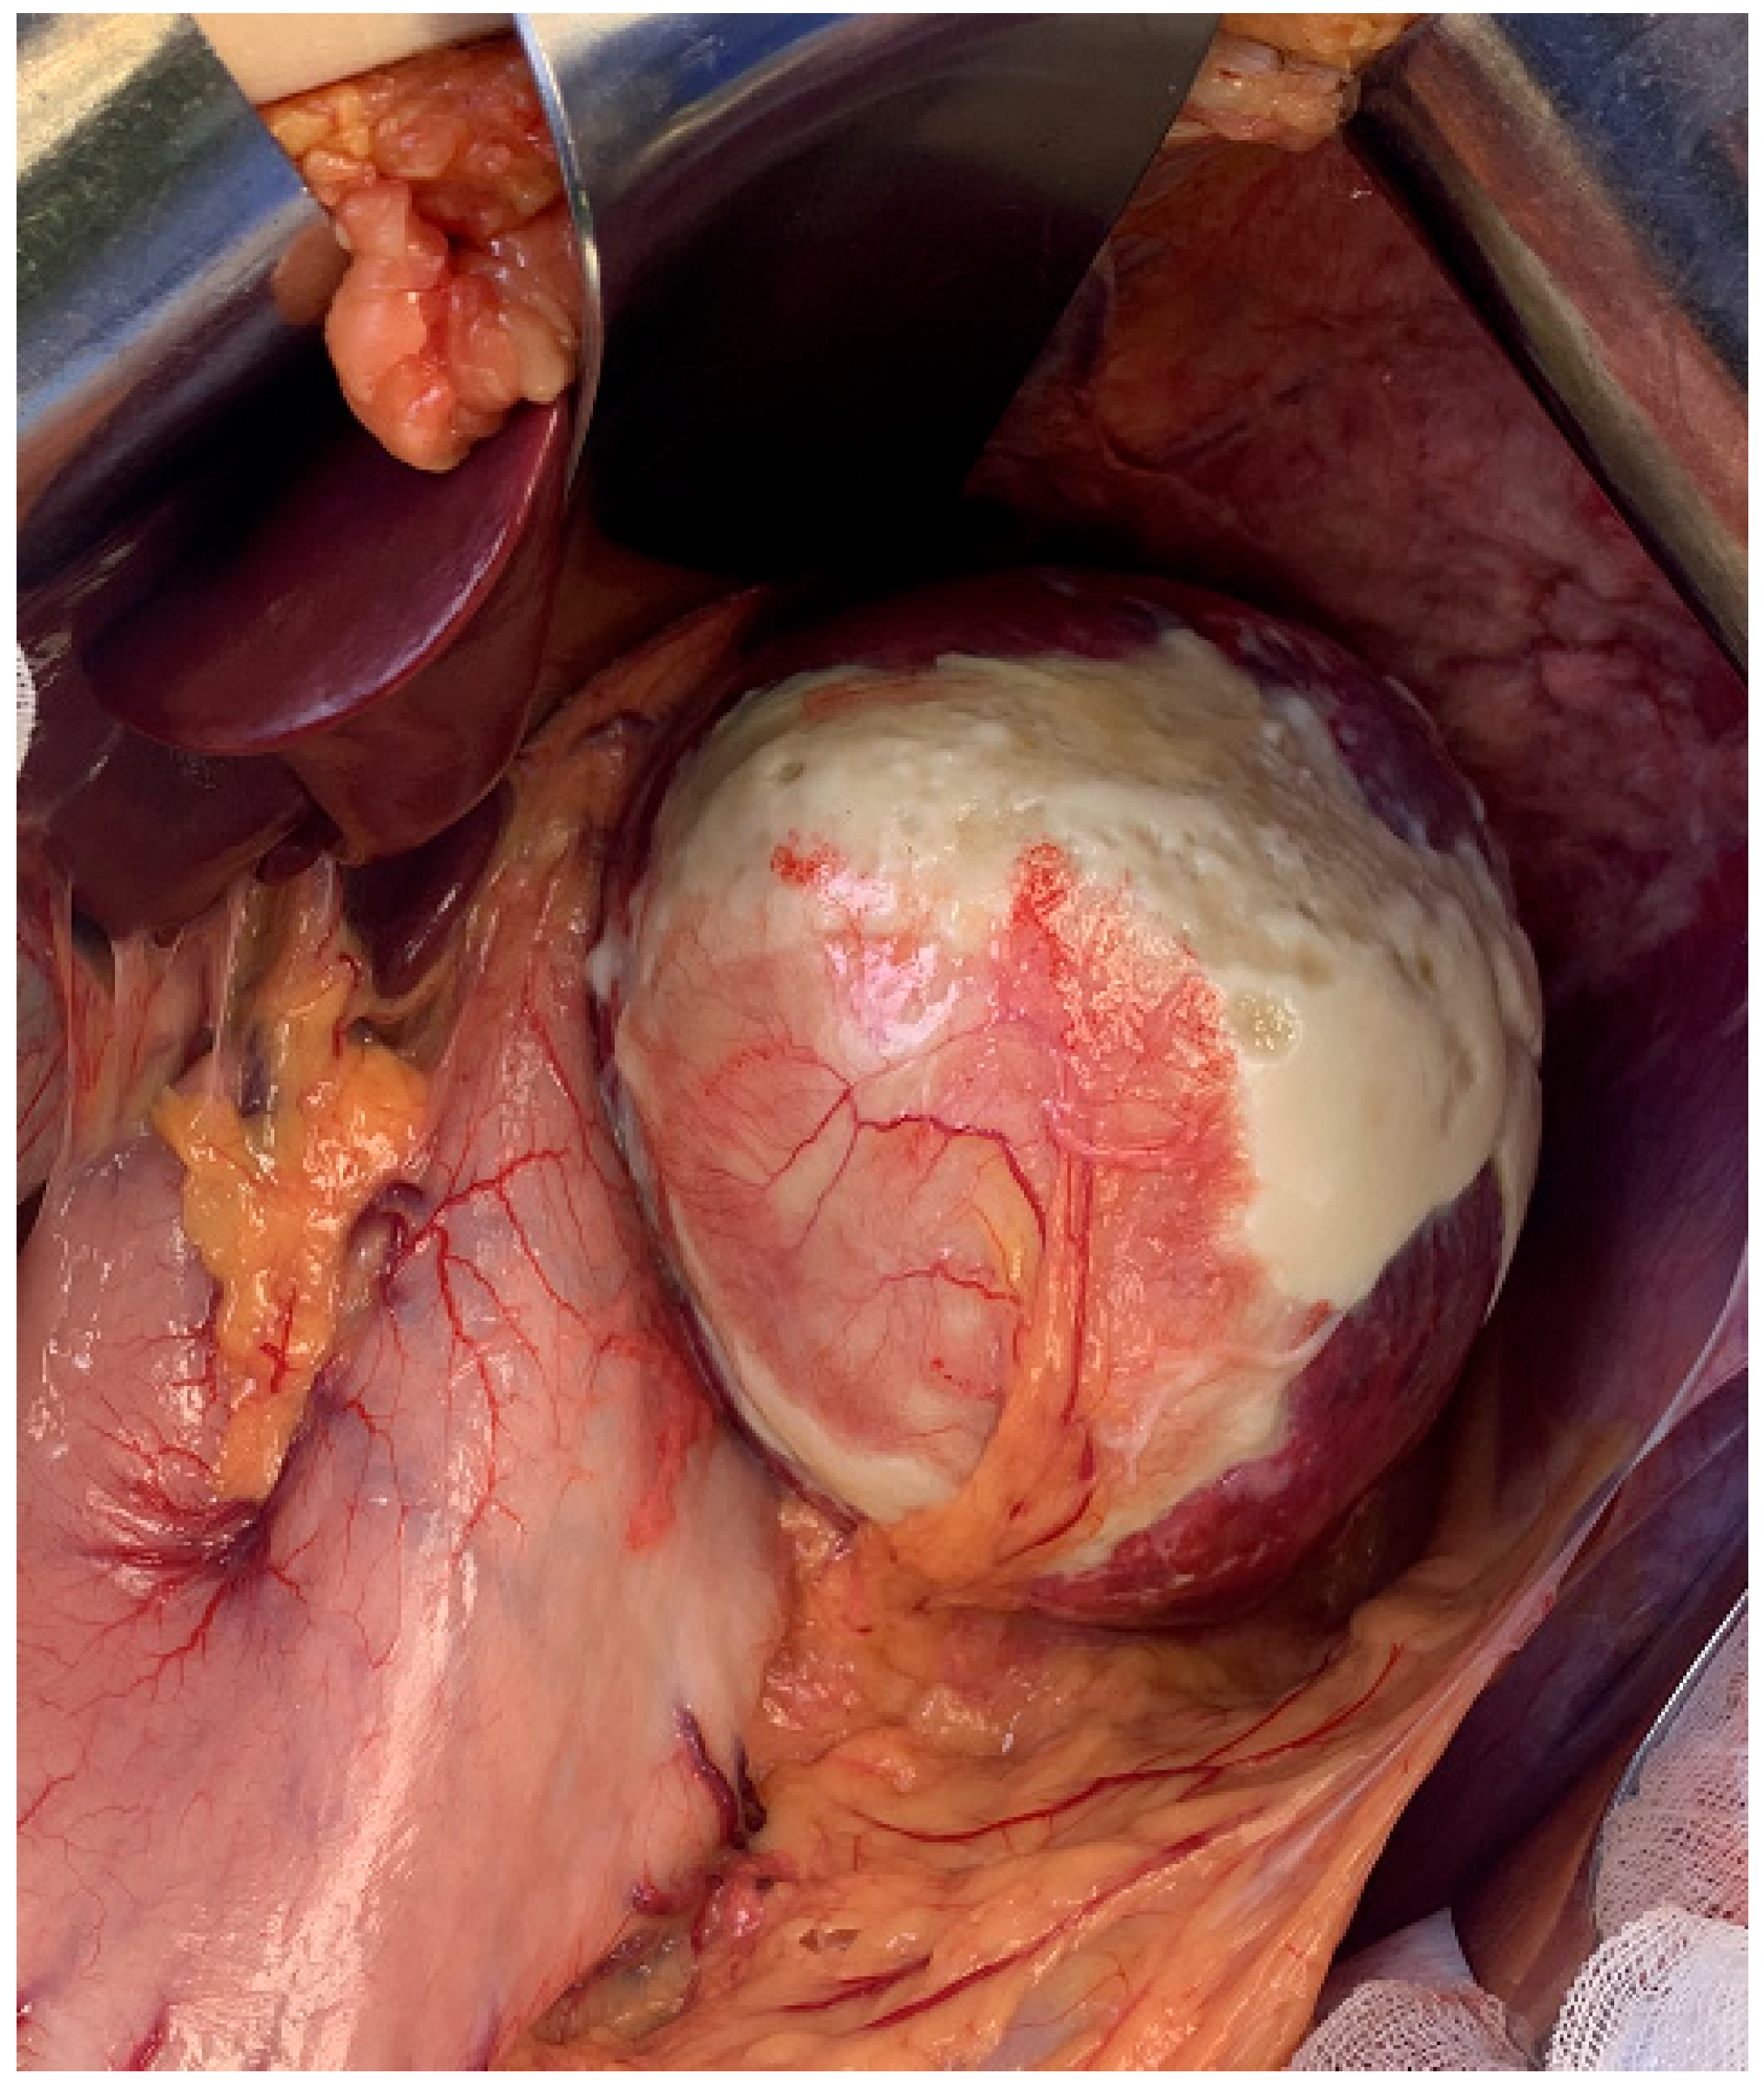

2. Case Presentation